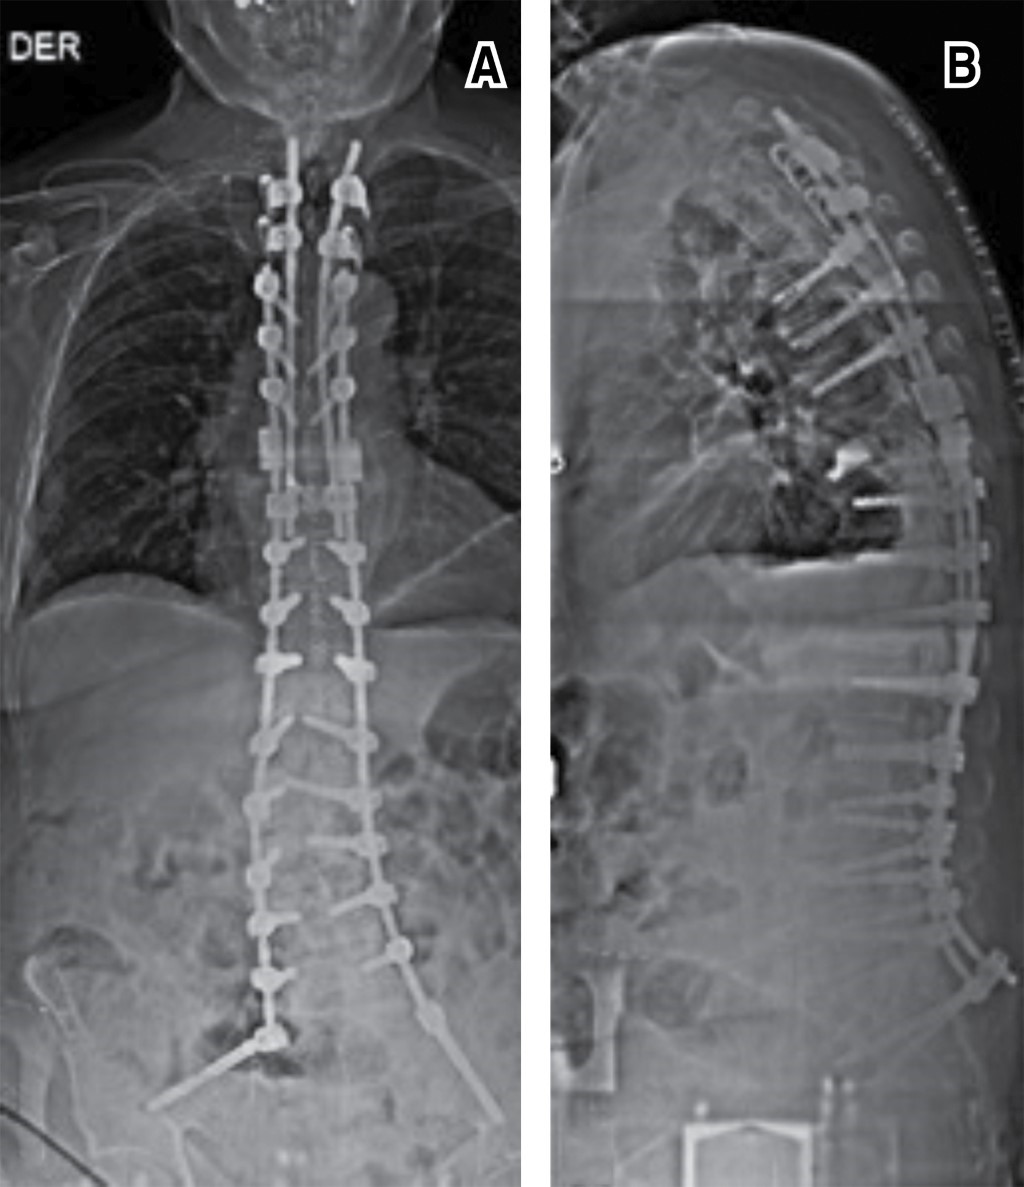

Paciente masculino con escoliosis lumbar degenerativa acompañado de enfermedad de Parkinson (EP). Se instrumenta únicamente los niveles necesarios para corrección de la deformidad coronal, como descompresión de los niveles con estenosis. A pesar de un control radiológico inmediato satisfactorio, en los días posteriores el paciente se aqueja de dolor a nivel de la columna torácica. Rayos X de seguimiento evidencian fractura de la vértebra más cefálica instrumentada. Debido a múltiples comorbilidades, se decide manejo conservador, esperando consolidación del segmento lesionado. Sin embargo, a pesar del tratamiento médico, es llevado cinco meses postoperatorio a sala de operaciones para prolongación de la instrumentación, realizando una transición de una fijación rígida a una semirrígida. El objetivo de la publicación es poner en contexto acerca de la dificultad que conlleva el manejo de un paciente que padezca EP combinado con algún padecimiento degenerativo de la columna.REFERENCIAS (EN ESTE ARTÍCULO)